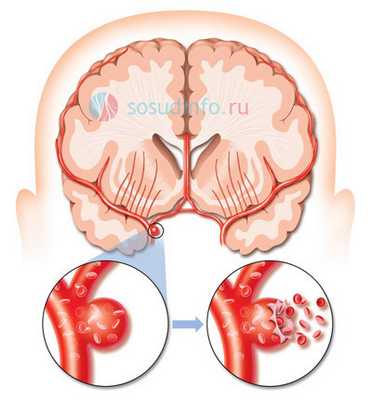

Из всех кровоизлияний внутри черепа субарахноидальное – одно из самых тяжелых, а причиной его в 85% случаев становится сосудистая мальформация. Кровь при этом проникает под мягкую мозговую оболочку, сдавливает мозг, нарушает движение ликвора, провоцирует тяжелые неврологические нарушения, а дислокация структур ствола мозга имеет высокий риск гибели в острейшем периоде заболевания.

разрыв аневризмы мозга

Разрыв аневризмы в обязательном порядке подлежит хирургической коррекции, но есть некоторые различия по срокам ее выполнения, которые связаны с индивидуальными особенностями течения патологии.